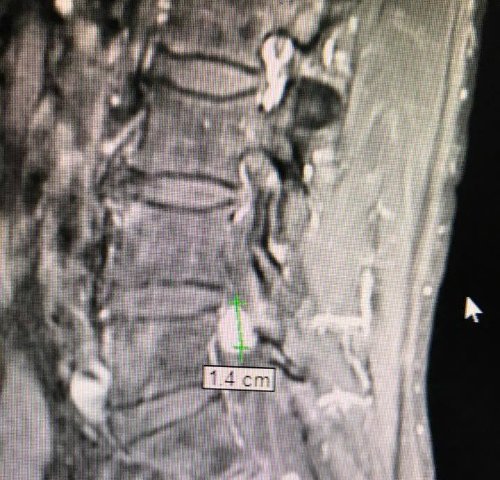

Suýt liệt vì khối u cột sống sau hơn 10 năm chữa đau lưng

Bệnh nhân TP HCM nhiều năm chữa thần kinh tọa vẫn không đỡ đau lưng, mới đây được phát hiện nguyên nhân là khối u...